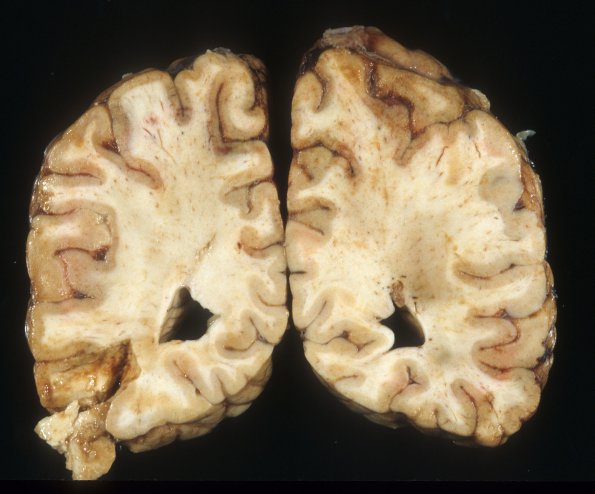

8A1,2 Laminar necrosis predominantly involves the superior aspects of the parieto-occipital lobe resulting in a granular discolored laminar ribbon